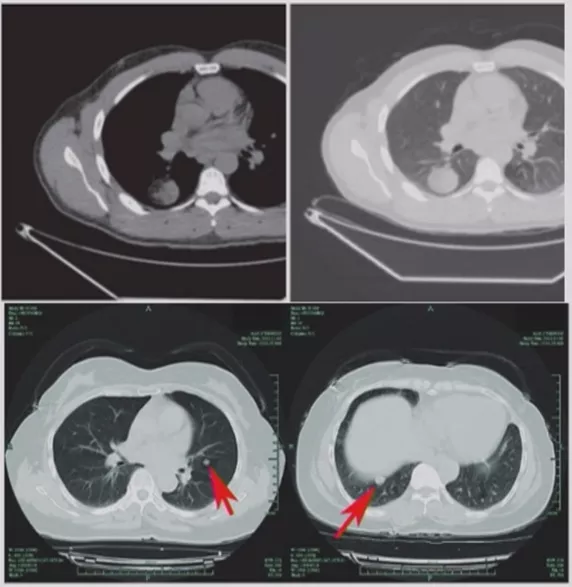

如上图所示,一般来说这么小的病灶我们可能忽略,但这个病人做了手术,不仅是恶性肿瘤,而且是微浸润腺癌。实际上我们在临床上要把这么多结节甄别出来,是十分具有挑战性的。病人一旦患有肺结节,也面临着很多问题,比如焦虑、心理压力等。所以我们既不能过度诊断,但也不能延误诊断。

在临床上经常手术切除后发现是AAH,关于AAH的病人是否需要手术还存在很大的争议,有的认为不需要手术,观察就可以。那么我们在术前怎么评判是否为AAH?其实具有一定特征。一般来说,多位于肺外周,多<5mm,圆形或类圆形,边界清楚,多发更常见,绝大部分是均匀的纯磨玻璃影,里边没有实性成分。组织学检查AAH呈轻度到中度非典型立方柱状上皮细胞沿肺泡和呼吸性细支气管上皮增殖,无浸润,这样在临床上诊断AAH应该没有问题。但是,如下图所示,这个病人是多灶性病变,现在多灶性结节有所增多,会给临床的处理上带来一定压力。

小细胞肺癌

小细胞肺癌以中央型多见,但是也有少数为周围型病灶。多为单个实性结节或肿块,可见分叶、毛刺、血管集束征、胸膜牵拉征。实际上我们很难从影像学上判断出小细胞肺癌的病理类型,往往是活检或者手术以后才能证实。如下图示,这属于I期的小细胞肺癌,进行手术的效果非常好。所以对于周围型小细胞肺癌,如果在结节很小的时候判断出来就做了手术,疗效非常好。我们知道小细胞肺癌是肺癌中治疗效果最差的,恶性程度是最高的。如果早期手术,仍然能够起到很好的效果。